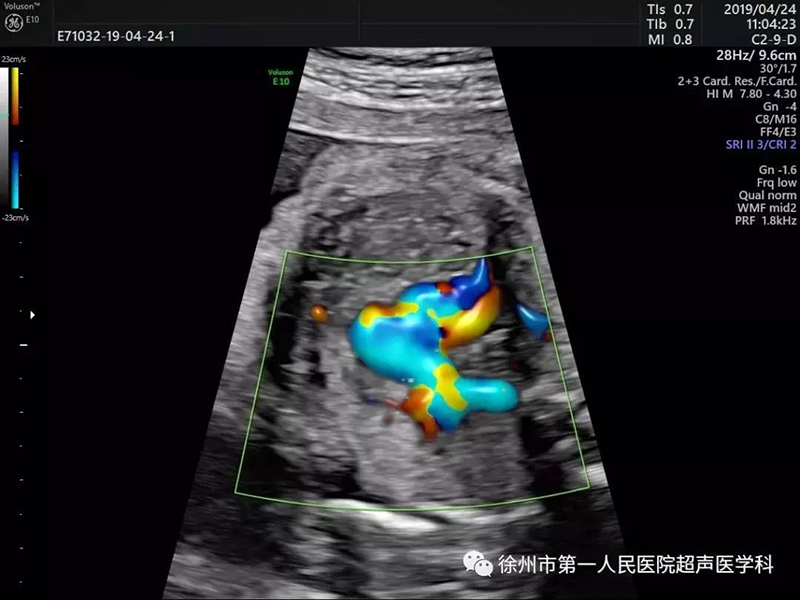

心臟超聲檢測(cè)更立體 評(píng)估更確切

心臟超聲檢測(cè)對(duì)于超聲圖像質(zhì)量及輔助的診斷工具要求非常高。美國(guó)GE Voluson E10優(yōu)異的圖像分辨率,能在四維空間內(nèi)展現(xiàn)立體的心臟結(jié)構(gòu)和功能,能更精準(zhǔn)檢查胎兒心臟發(fā)育情況。

E10具備一整套卓越的胎心成像技術(shù)(STIC),支持從胎兒心臟結(jié)構(gòu)到心功能的分析,是胎兒心臟檢測(cè)評(píng)估領(lǐng)域的技術(shù)領(lǐng)導(dǎo)。雙平面成像技術(shù)可真實(shí)呈現(xiàn)胎心結(jié)構(gòu)、臍帶、血流變化,幫助臨床醫(yī)生及時(shí)作出確切診斷,是目前超聲領(lǐng)域診斷的利器。